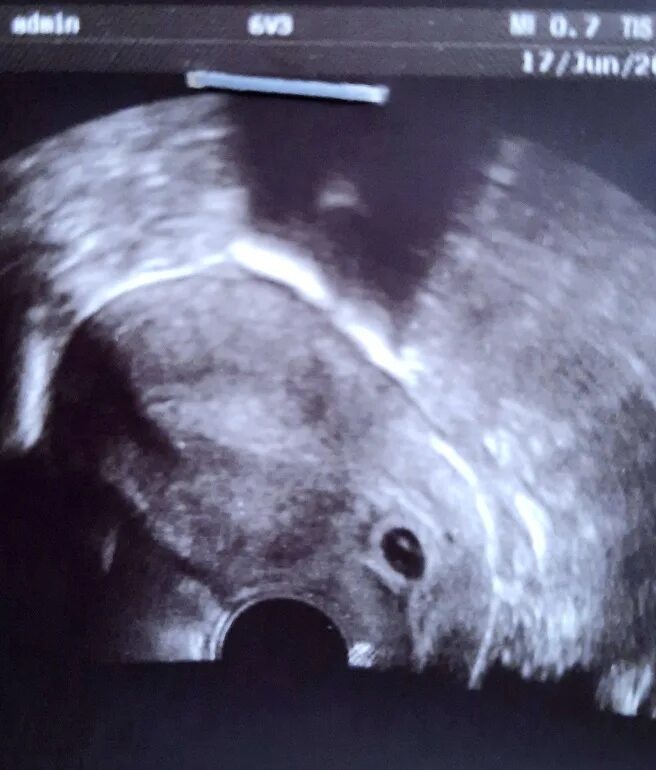

Беременность 5 мм